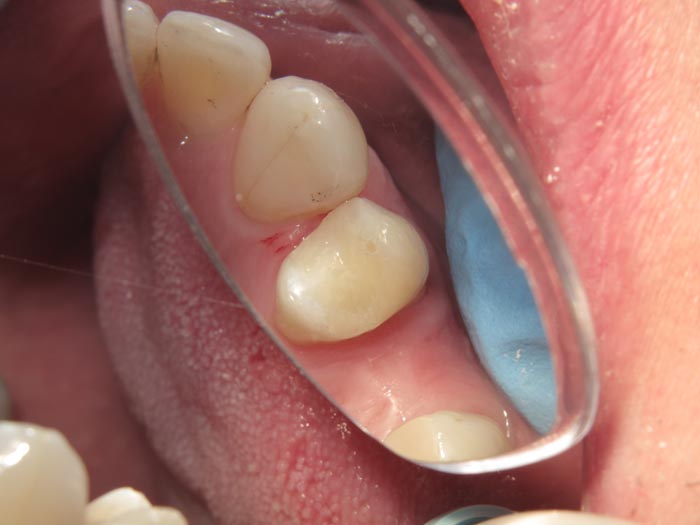

Case 1

A 37-year-old patient presented for treatment after years of neglect. After administering anesthetic and placing an Isolite isolation device, we prepared teeth #10–12 and restored them

with Activa Bioactive-Restorative composite.

• Figure 1

• Figure 2

• Figure 3

• Figure 4

• Figure 5

• Figure 6